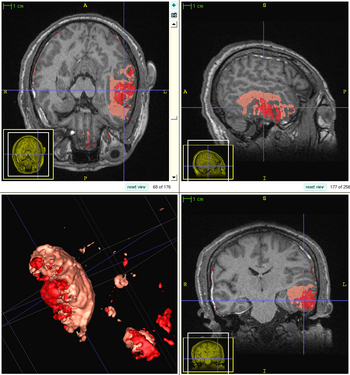

We propose a multi-modal image segmentation framework for longitudinal TBI images. The framework is initialized through manual input of primary lesion sites at each time point, which are then refined by a joint approach composed of Bayesian segmentation and construction of a personalized atlas. The personalized atlas construction estimates the average of the posteriors of the Bayesian segmentation at each time point and warps the average back to each time point to provide the updated priors for Bayesian segmentation. The difference between our approach and segmenting longitudinal images independently is that we use the information from all time points to improve the segmentations. Given a manual initialization, our framework automatically segments healthy structures (white matter, grey matter, cerebrospinal fluid) as well as different lesions such as hemorrhagic lesions and edema. Our framework can handle different sets of modalities at each time point, which provides flexibility in analyzing clinical scans.The segmentation of acute and chronic images using our framework are presented in the following figures. This work has been submitted to SPIE Medical Imaging 2012 [1].

1

2